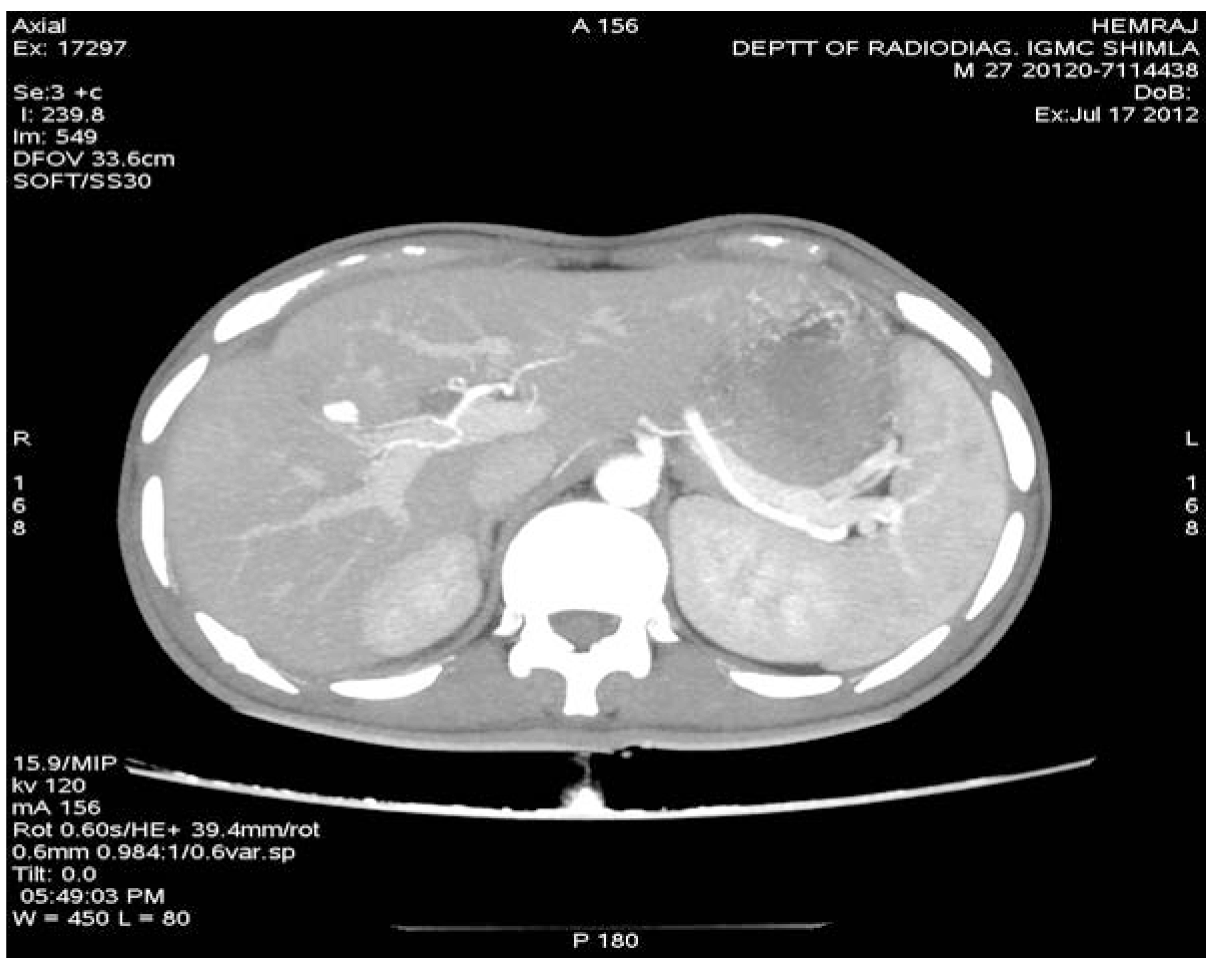

A 27-year-old male presented with complaints of one episode of hematemesis seven days back and melena for seven days. There was a history of roadside accident one and a half months before with grade IV liver injury, revealed on computed tomography (CT) scan of the abdomen. Patient was managed conservatively in Department of Surgery and discharged from hospital after one week in stable condition. On examination, the patient was anemic, pulse 110/min, blood pressure 80/50 mmHg with postural fall in blood pressure. The systemic examination was normal. Clinical possibility of upper GI bleed was kept. Emergency investigation revealed hemoglobin 4.5 g/dL, TLC 4900/mm3. BU 30 mg%, S. cr.-1.0 mg%, and electrolytes Na-135 mEq /L, K-4.1 mEq/L, Cl-105. The nasogastric tube drainage was persistently revealed altered blood. The patient was stabilized with three units of blood transfusion and emergency esophagogastroduodenoscopy was done. The esophagogastroduodenoscopy revealed alerted blood in the stomach with large clot in the fundus but source was not evident, first and second part of duodenum was also normal, but blood was present. On visualizing the ampulla, there was evidence of blood coming from ampulla. Emergency computed tomography angiography revealed pseudoaneurysm in segment VIII of liver involving segmental branches of right hepatic artery with active bleeding with communication with biliary radicals, with blood in gallbladder, common bile duct and second part of duodenum with subcapsular hematoma in segment VIII. (Figure 1) The digital selective arteriography revealed pseudoaneurysm from segmental branches of right hepatic artery. (Figure 2) Embolization was done and post embolization digital selective arteriography revealed complete non opacification of pseudoaneurysm. (Figure 3)

Figure 1: Axial section computed tomography angiography showing pseudoaneurysm in segmental branches of right hepatic artery.